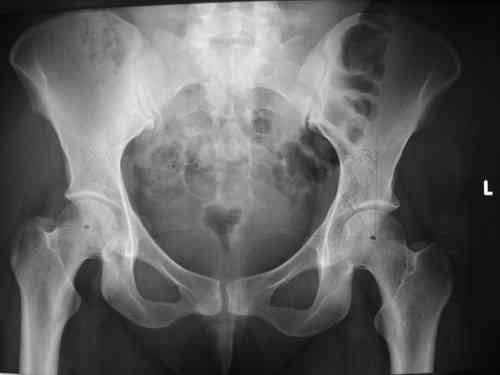

Спасибо за клинические примеры и комментарии. Если честно то просто восхищен представлеными R-ммами (классно сделали!!!). По поводу обсуждаемого больного: конечно КТ и дополнительные R-ммы сделаем. Но хочу напомнить, что после травмы прошло более 6 лет, на сегодняшний день клинически еще и R-ки признаки нестабильности эндопротеза( как бедренного компонента так и чашки). Хочется определиться как делать в аппарате или одномоментно открыто. Лично я склоняюсь к аппаратному лечению на первом этапе.

прилагаю пример с такой же давностью травмы, репонировали аппаратом